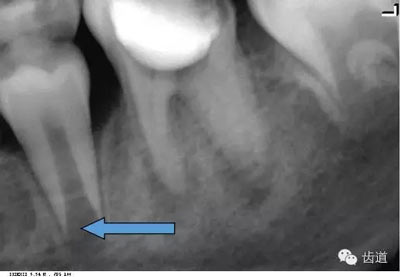

3)頦孔:

位于前磨牙根尖區(qū)域,為一大致圓形密度低的影像。頦孔位置變異大,多位于第二前磨牙根尖稍下,注意與根尖周病變區(qū)別,其要點(diǎn)是牙周膜及其骨硬板是否連續(xù)不斷。